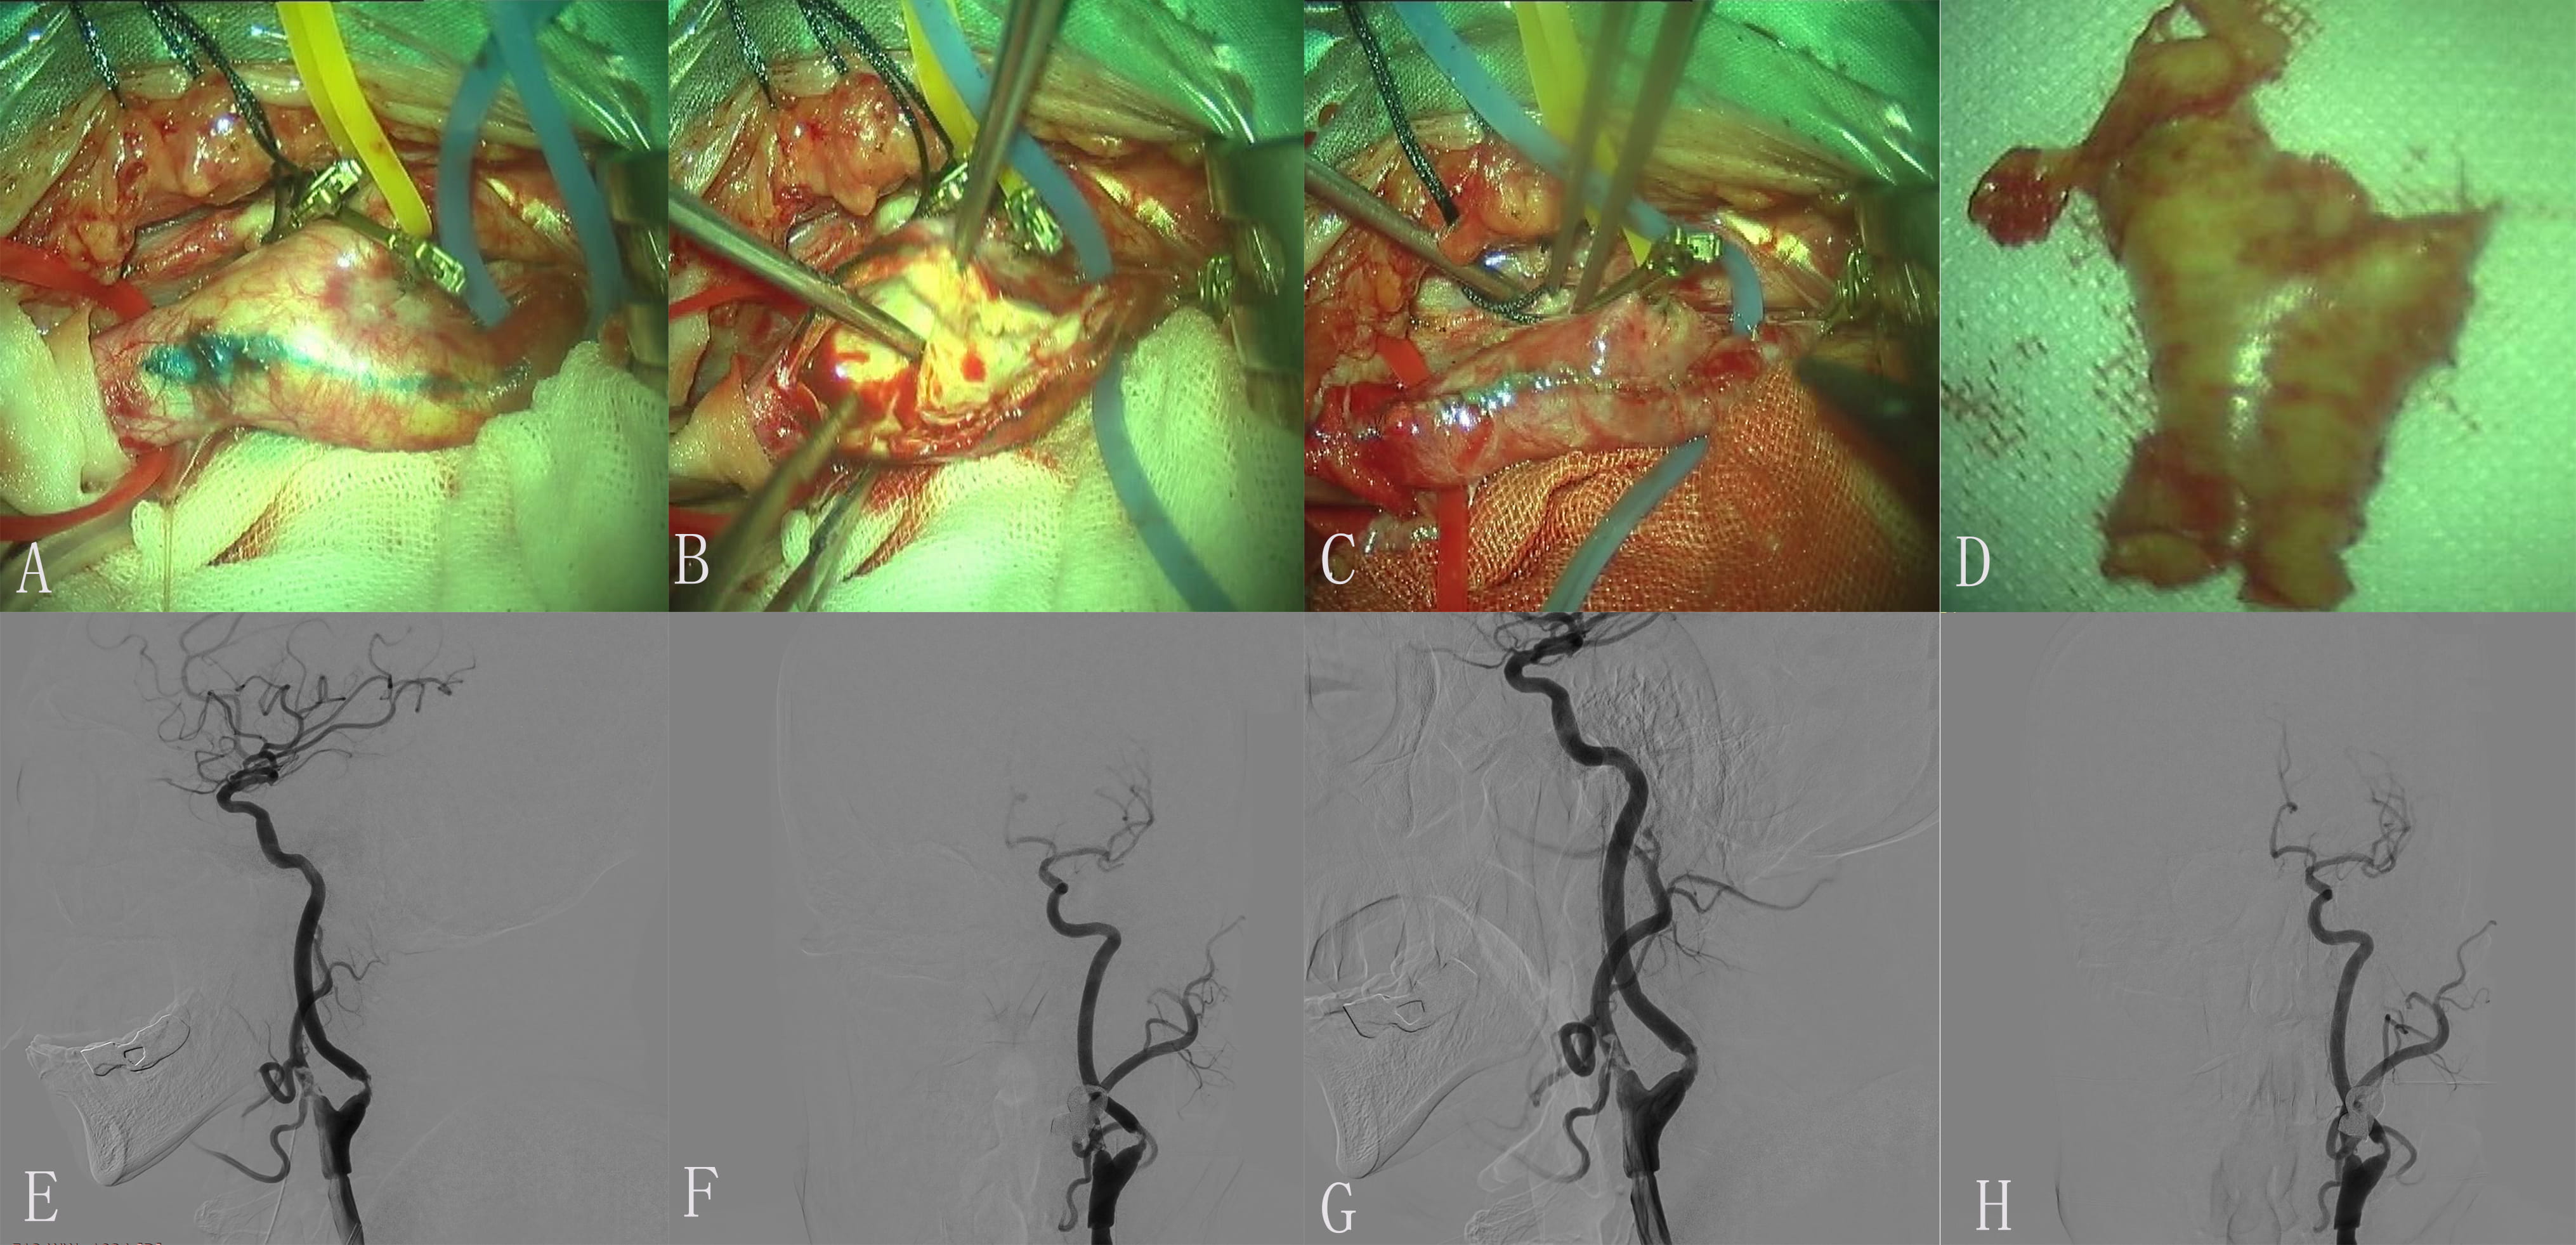

Under general anesthesia, the left CCA, ICA and ECA, STA were exposed. After blocking up the artery, the anterior wall of the carotid artery is incised. The plaque presented as unstable, the intima of the ICA was carefully treated and the fragments were removed. Suture the carotid artery, leave a needle without ligation. The carotid sheath was sutured layer by layer, the right lower limb was braked, and the femoral sheath was fixed well. The muscle tension of limbs was normal. After operation, the patient had a head CT scan, which ruled out an ICH. DSA demonstrated that the left MCA was occlusion (Fig. 3). Then, through a 6-French introducer sheath in the RFA and after the administration of heparin (3000 U), a 6-French guiding catheter (Cordis Corporation, Bridgewater, NJ, USA) was advanced in the proximal left CAA. DSA show that embolus was formed in a position with a large angle of CEA on left ICA. The imaging of ICA was significantly improved after 0.5 mg tirofiban was administered to the artery.

Fig. 3.Images of Case 3. Color Doppler ultrasonography of carotid artery on admission showed initial severe stenosis of the left internal carotid artery (ICA). The stenosis is greater than 90%. (A) Each branch was blocked by exposed responsibility carotid artery. (B) The endometrium of the common carotid artery (CCA) was dissected longitudinally and presented plaque. (C) Incision suture. (D) Intimal plaque. (E,F) Embolus was formed in a position with a large angle of carotid endarterectomy (CEA). (G,H) The imaging of ICA was significantly improved after 0.5 mg tirofiban was administered to the artery.